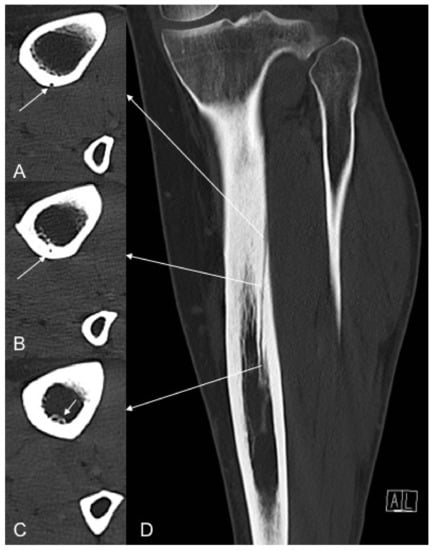

TNAC was identified with an outer and inner foramen and a traversing cortical canal (Figure 2).

Figure 2. Subsequent axial (AC) and coronal (D) reformatted images in bone window indicating the foramen of the nutrient artery canal on the outer cortex (A) (white arrows), cortical canal course (B) and inner cortex (C) (white arrows).